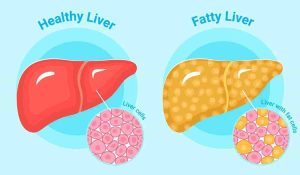

راهنمای کامل بیماری کبد چرب | از پیشگیری تا درمان